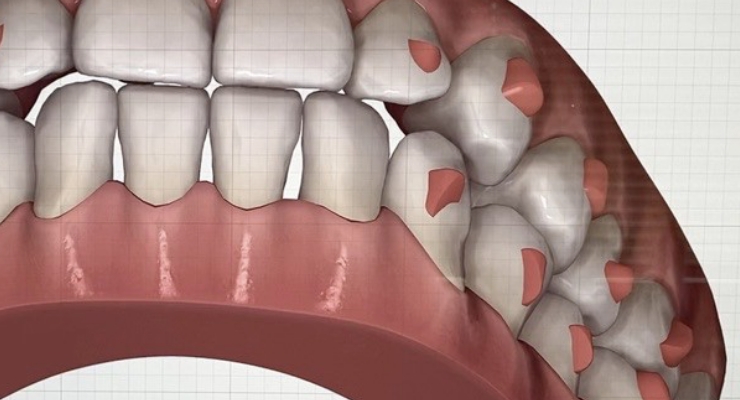

ただキレイに並べるだけでなく、顎関節、かみ合わせにもこだわったマウスピース矯正が当医院の特徴です。

マウスピース矯正とワイヤー矯正のいいとこ取りをし、患者さまに歯列状況に合わせ最適な治療を行います。

• 治療前に歯並びをシミュレーション 治療前に歯並びをシミュレーション